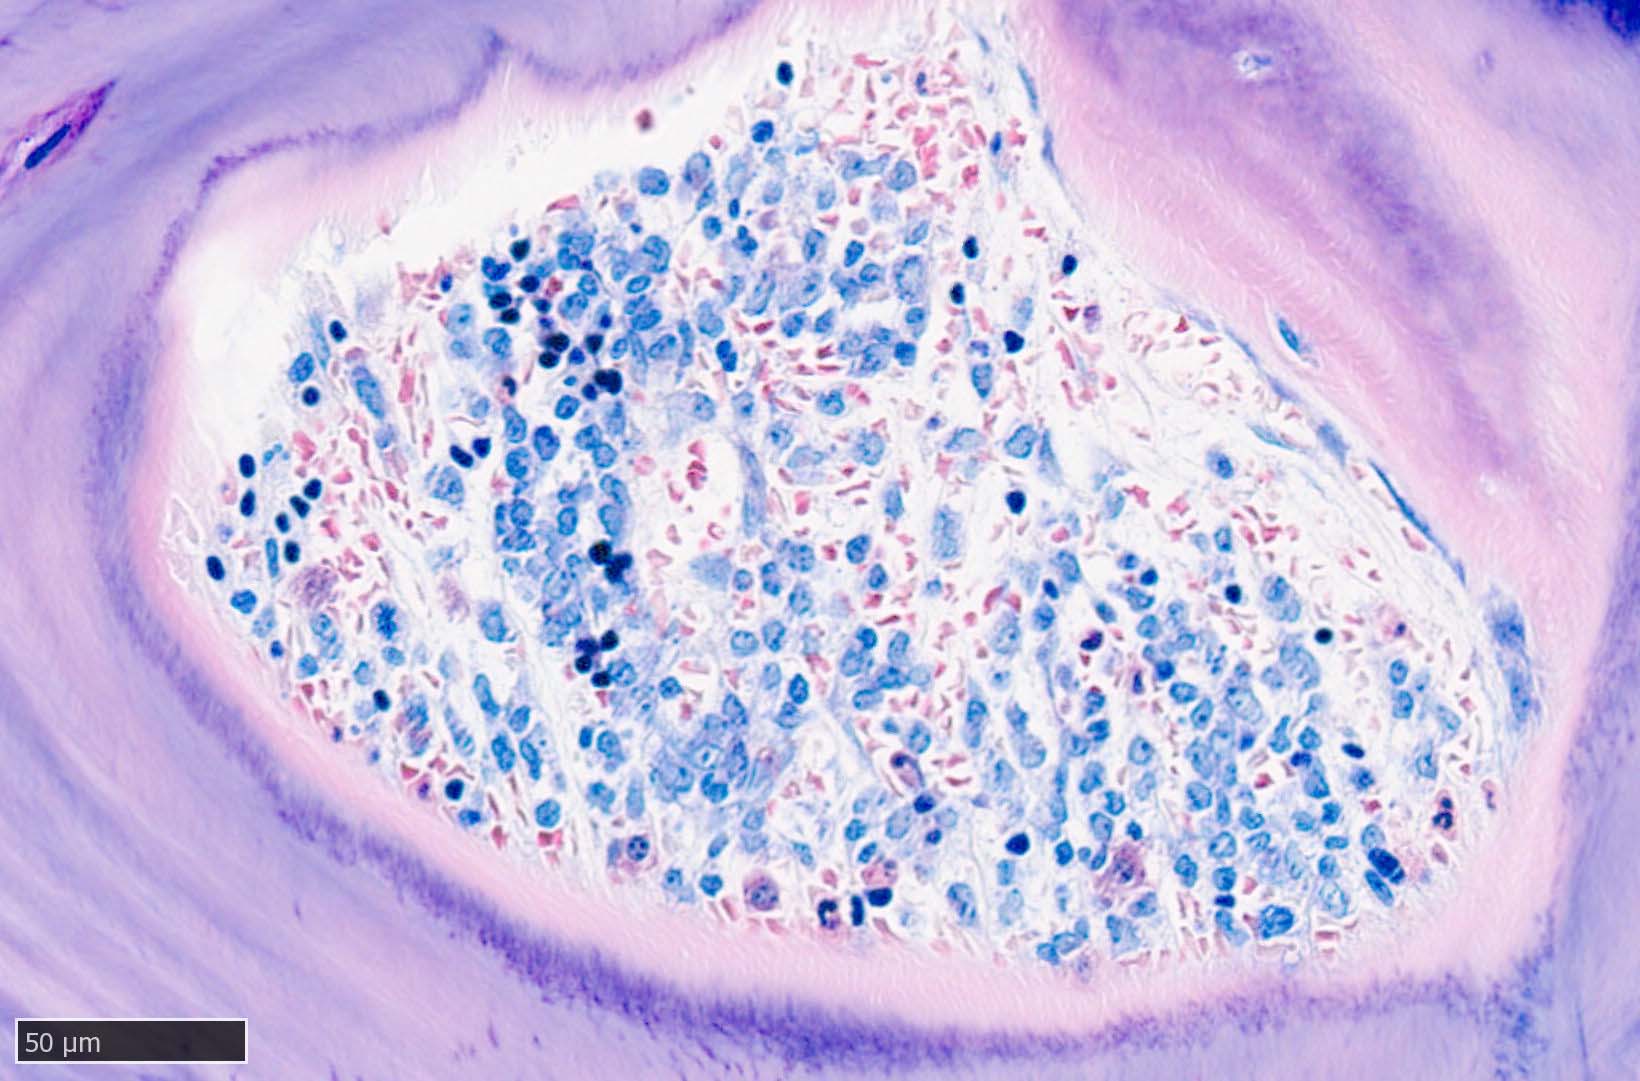

本例ではviableな腫瘍細胞がハーバース管と考えられる管内に認められた.(髄腔とハーバース管腔は解剖学的に同じ場所といえるのか?)

ハーバース管は緻密骨内の骨構造であり, 管内には動静脈, 脈管周囲リンパ管, 神経線維が入る. 解剖学的に海綿骨骨髄腔とは異なる空間構造と考えられる.--viableな腫瘍細胞の存在はリンパ管、血管内への腫瘍浸潤と考えられる.

ハーバース管